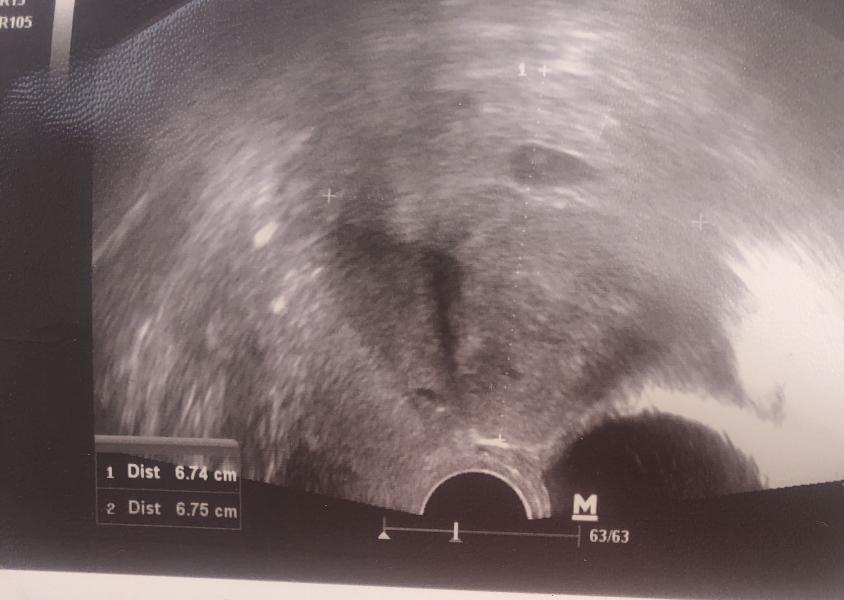

Девоньки это все таки залёт😂а я думала я просто социопатом стала ,а нет пырышка пупырышка добавляет )ну что ж держись крепко)6 недель ровно сердце бьется )на учет только 15 числа талончик )ну и ладно)я не тороплюсь)кто с мной рожать в январь/февраль?)